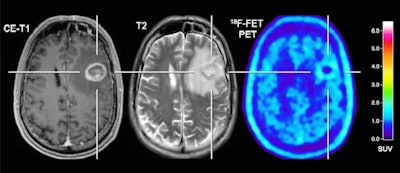

German and Swiss researchers achieved an accuracy of 85% when using FET-PET and easily calculated tumor-to-brain ratios to distinguish relapses of brain metastases from changes related to treatments that included immune checkpoint inhibition or targeted therapy. By doing so, F-18 FET-PET also bested the performance of contrast-enhanced MRI.

"F-18 FET-PET provided additional important clinical information for treatment response evaluation beyond the information provided by contrast-enhanced MRI alone, i.e., in terms of identification of false-positive or false-negative MRI findings," added the authors, led by Dr. Norbert Galldiks from University Hospital Cologne.

Conversely, there is evidence -- albeit limited -- that PET imaging with radiolabeled amino acids might advance treatment evaluation. Amino acid uptake, as with FET, increases in neoplastic tissue, which could indicate cancer cell growth, and it has low uptake in normally functioning brain tissue. As a result, there is enhanced tumor-to-brain contrast for better interpretation, the authors noted.

Using a tumor-to-background ratio of 1.95 as a threshold to differentiate brain metastases from treatment-related changes, the researchers could significantly distinguish relapse of brain metastases from treatment changes with an accuracy of 85% (p = 0.003) with FET-PET. The modality also identified patients who were both responders and nonresponders to treatment that included immune checkpoint inhibition or targeted therapy with accuracy, sensitivity, and specificity between 80% and 83%.

In comparison with MRI, FET-PET provided additional information in four (31%) of 13 patients who showed treatment-related changes beyond contrast-enhanced MRI alone. For example, FET-PET confirmed a "significant decrease of metabolic activity" in two of the four cases, whereas MRI indicated metastatic disease progression in both patients.